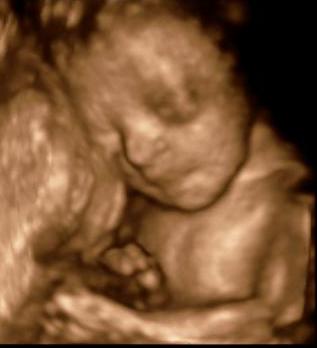

Akkor már éreztem, hogy gond van. A tény az, hogy a jobb oldalon egy darab kis 8 mm-es tüsző van.

Ami viszont roppant érdekes, hogy a bal oldalon is van egy 12 mm-es. Na akkor mit látott vasárnap?